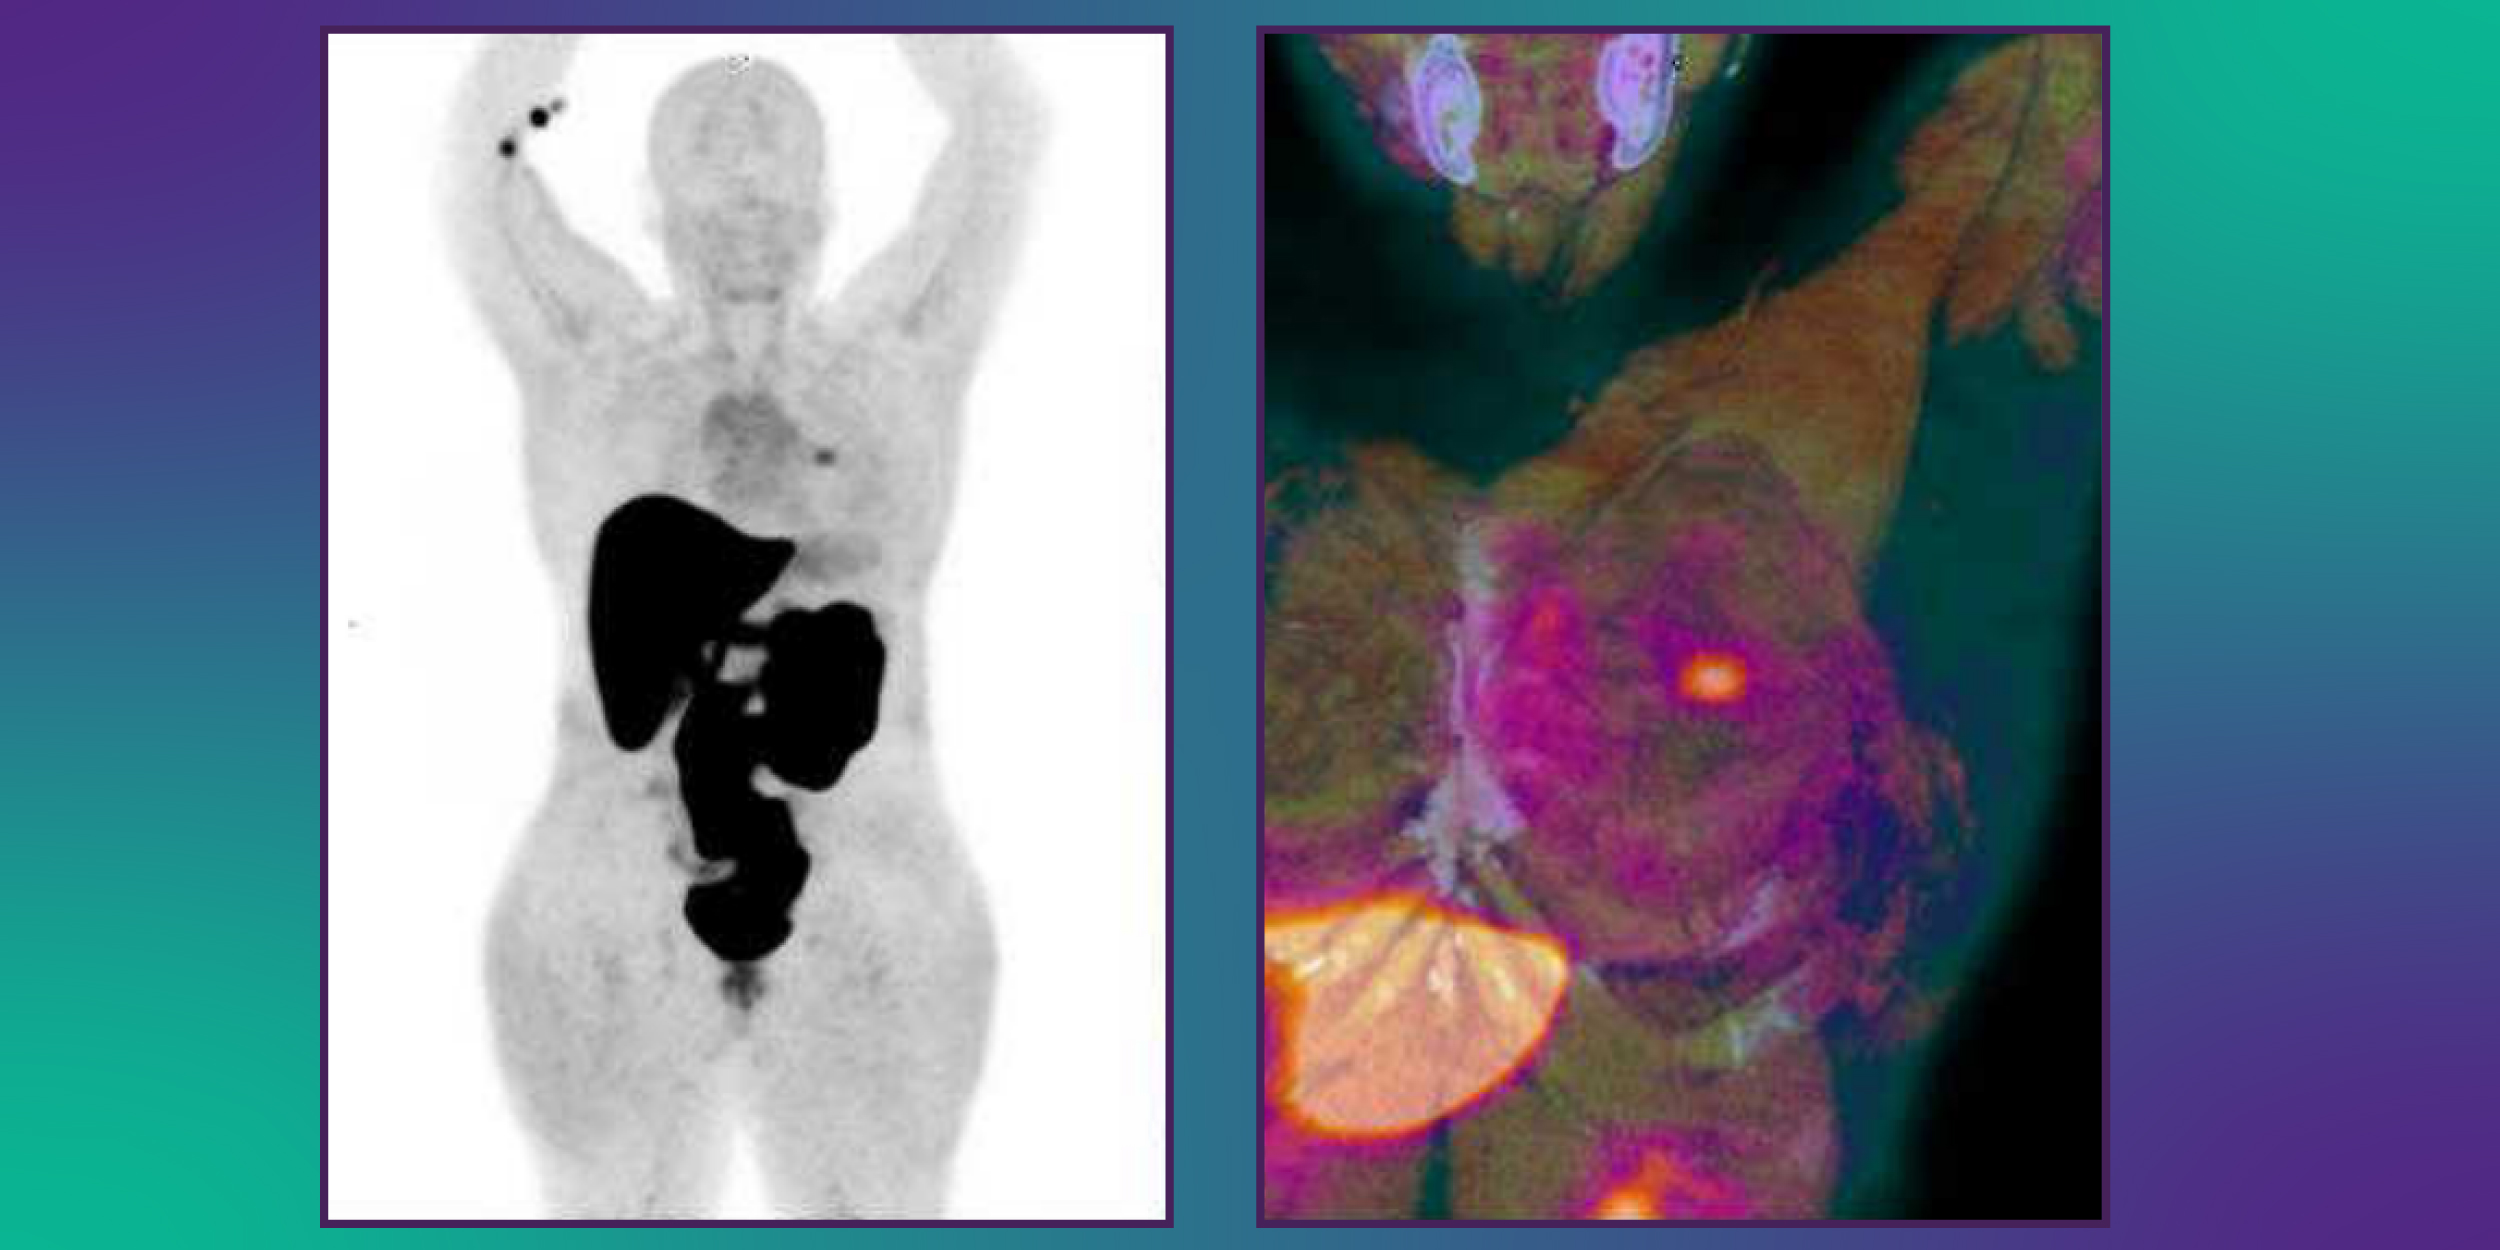

Temos o orgulho de anunciar que o IDS realizou o primeiro exame de PET-CT com Fluorestradiol F18 em Sorocaba e região! Essa inovação reforça nosso compromisso em trazer o que há de mais moderno e avançado em diagnóstico por imagem.

PET / CT